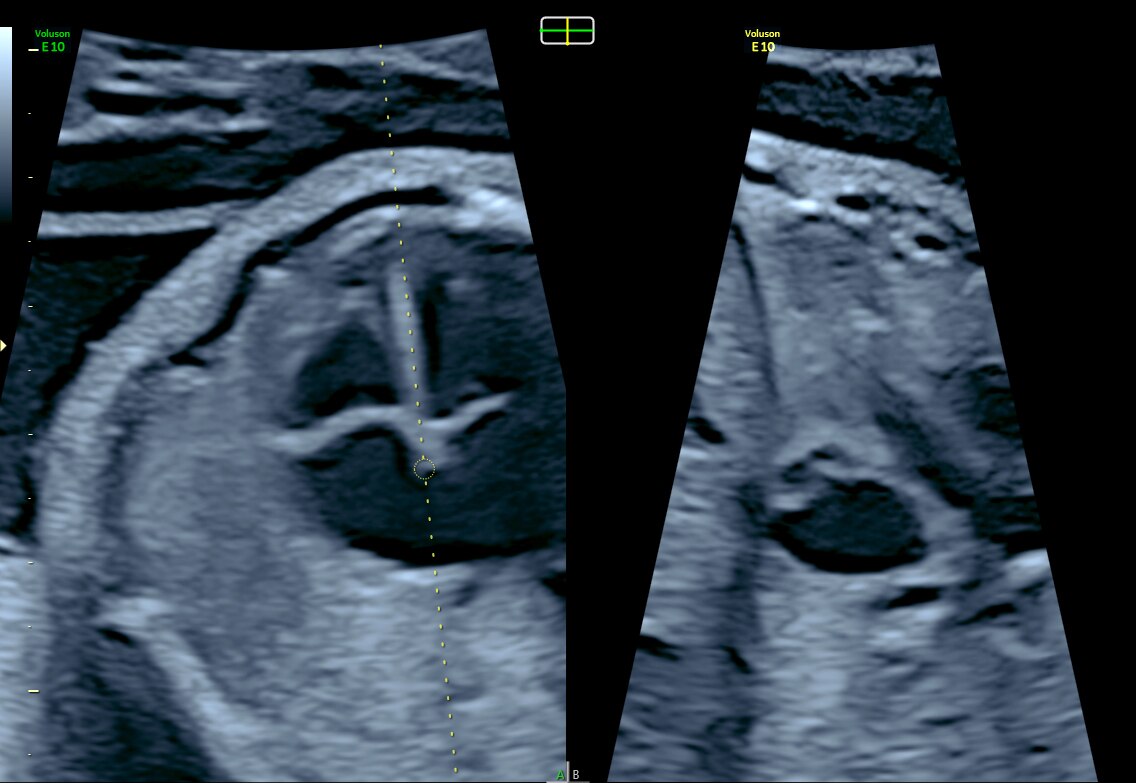

View of intraventricular septum with e4D Bi-plane imaging